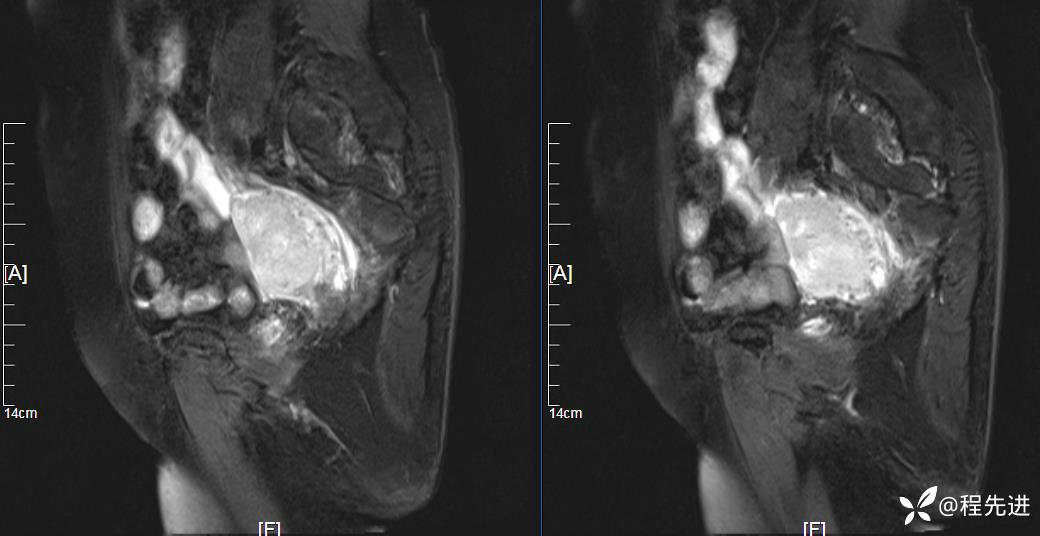

MRI平扫:

T2压脂:

T2:

T1:

患者性别:女

患者年龄:76岁

简要病史:下腹痛伴发热半月余

实验室检查:肿瘤指标均正常